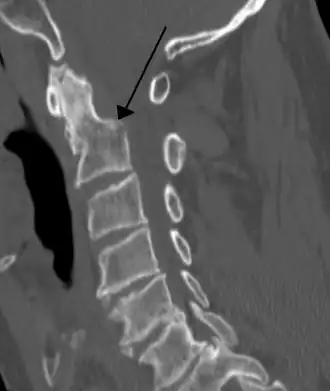

Na tomografia computadorizada ou radiografia, uma fratura cervical pode ser visualizada diretamente. Além disso, sinais indiretos de lesão pela coluna vertebral são incongruências das linhas vertebrais,[6] e/ou aumento da espessura do espaço pré-vertebral:[7]

- Tomografia computadorizada de linhas vertebrais congruentes normais.[8]